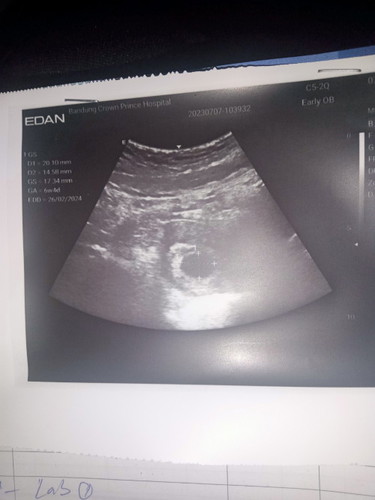

เราไปซาวด์ตอน6สัปดาห์เจอแต่ถุงตั้งครรภ์ปกติมั้ย แม่ๆซาวด์เจอน้องตอนกี่สัปดาห์กันคะ กลัวท้องลมมากคะ #คุณแม่ๆช่วยแนะนำหน่อยค่ะ #ขอบคุณสำหรับคำตอบค่ะ #ขอคำแนะนำหน่อยค่ะ #ท้องแรกคะ #ขอบคุณล่วงหน้านะคะ

ไปหาหมอตอน6วีค หมอซาวด์ดูเจอถุงตั้งครรภ์ พอวันก่อนเหมือนมีเลือดสีน้ำตาลเลอะกางเกงในนิดหน่อย และเมื่อวานเลยไปหาหมอ หมอซาวด์ดูถุงตั้งครรภ์ไม่โตขึ้นค่ะ และไม่มีตัวอ่อน หมอสัญนิษฐานว่าท้องลม แนะนำให้ขูดมดลูกค่ะ หมอบอกนัดอีก2อาทิตย์ถ้ายังไม่โตอีกนัดวันขูดได้เลยค่ะ

ซาวด์ครั้งแรก6สัปดาห์เจอแต่ถุงเหมือนกันค่ะหมอบอกอาจจะท้องลม หมอให้เวลา1เดือนถ้ายังไม่เจอคือท้องลม พอหมอนัดซาวด์อีกทีก็เจอน้องเลยค่ะเจอตอน10สัปดาห์ แม่อย่ากังวลนะคะ น้องยังเล็กมากๆเลยยังไม่เห็นค่ะ

ของเเม่บ้านนี้ไปซาวด์ครั้งเเรก 6w เจอเเต่ถุงเหมือนกันค่ะ ไปซาวด์อีกรอบ8-9w เจอน้องเเล้วก็เห็นหัวใจน้องเเล้วค่ะ เเม่ไม่ต้องกังวลนะคะ บ้านนี้ก็เป็นเหมือนกัน เดี๋ยวพออายุครรภ์8-9week ก็เจอน้องค่า 🥰

บ้านนี้ซาวตอน6วีค เจอแต่ถุงตั้งครรภ์เหมือนกันค่ะ มาเจอน้องอีกที ตอน9วีค ค่ะ ตอนนี้ท้องได้ 14w2dแล้วค่ะ แม่ใจเย็นๆนะคะ เดี๋ยวก้อเจอน้องค่ะ☺️☺️